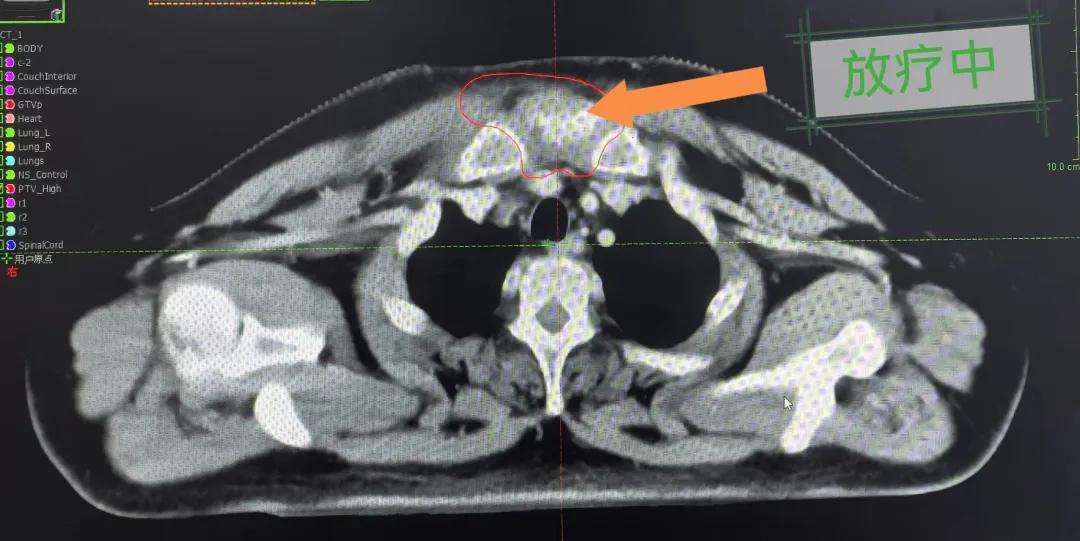

隨后,趙亮主任帶領放療團隊以最快的速度完成了患者的放射治療計劃,在保證放療精準打擊腫瘤的同時,利用先進的三維立體精確放療技術,最大限度的避免心臟、肺部的損傷發生,整體治療精準度達到1mm以內。經過10次的放射治療后,患者疼痛已明顯減輕,胸部腫物肉眼可見的縮小,患者及家屬臉上終于露出久違的笑臉。

治療期間,患者沒有出現明顯不適,治療結束后,患者胸壁腫物由最初8cm縮小至約1cm,后患者至外科行手術治療。